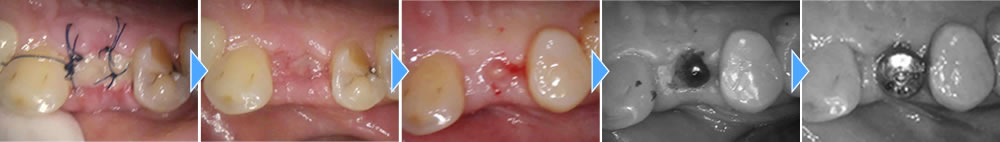

オペは傷口を最小限に抑えたため、痛みはほぼ出ず、痛み止めもほとんど服用せず落ち着きました。

上部構造の装着・治療完了

インプラントと顎骨がきちんと結合していることを確認後、上部構造を装着して治療完了です。治療後は固いものも問題なく噛むことができ、何より見た目が普通の歯とほぼ変わらず、大変満足していただくことができました。